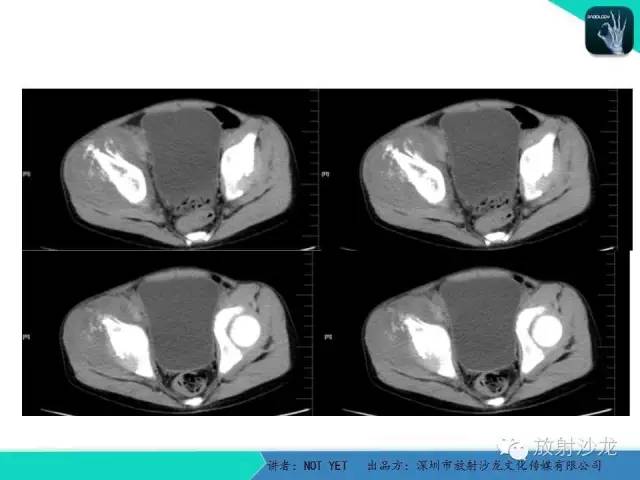

【病例】右侧髂骨Ewing肉瘤1例CT影像表现